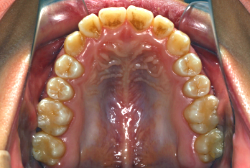

上下顎前突

上下とも歯列が前方に突出していて口を閉じにくい、または口を閉じたときに口元が前に出ている状態を上下顎前突といいます。

歯並びがきれいでも前歯が前に傾いていて、口元に突出感があることもあります。前歯が外に傾くと唇が押し出されることになりますので、少し不満げな口元になってしまいます。

「上の前歯の凸凹」という主訴で来院したケースです。確かに上の左右二番目の歯が内側に引っ込んでいて、凸凹が目立つ状態です。歯並びの凸凹を矯正学では 叢生(そうせい)と言いまして、確かにご本人的にはそこが気になるのですが、矯正学的には前歯の前突の方がより問題となるケースです。

初診時の写真をご覧いただくと、何となく前歯が前傾しているのが感じられると思うのですが、よく見ると上の歯だけでなく、下の前歯も前傾しているのがわかります。このように上の前歯も下の前歯も両方外向きになっている症状のことを、「上下顎前突」と言います。こういうケースの場合は上下左右の小臼歯を抜く(つまり4本抜歯する)ことで配列の中に隙間を作り、その隙間を利用して配列を揃えるだけでなく、 前歯を内側に入れていく治療をします。

治療前後の口元の変化です。前歯の角度が大きく変わりました。治療前は外向きの前歯に押されて、口元がふくらみすぎの状態でした。黄色の線は鼻の頂上と顎の先端を結んだ線で、審美線と言います。審美線と唇はあまり接触しない方が良いと考えられています。矢印の部分がかなりラインオーバーしています。治療後はよりスマートで美しい横顔になりました。このように歯並びを直すと、唇の表情ひいてはお顔全体の表情にも良い変化が生まれます。